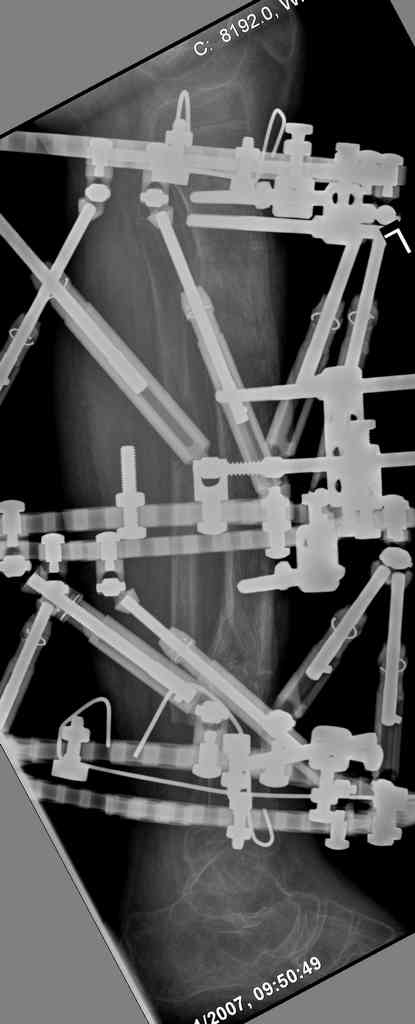

4. Никто не назвал методику, которая мне представляется наиболее удачной - тибиализация малоберцовой кости. Пластинку, конечно, придется убрать. Нужно наложить кольцевой Илизаров,

томировать малоберцовку на уровне дефекта, закрыто пересечь большеберцовую кость у основания острого края проксимального отломка - и подтянуть фрагмент малоберцовой кости в зону дефекта большеберцовой спицами с упорными площадками. Не обязательно при этом выводить строго в центр, достаточно сращения при боковом касании отломков - малоберцовая кость оттеснит как раз "сосульку" в сторону, и томированные края берцовых костей срастутся между собой. Есть еще ряд нюансов - готов расписать со схемами в случае, если будет принято решение в пользу этой методики.

5. Ну и чтобы не быть голословным. Молодой человек подорвался на фугасе (Чечня, 2005 год). Свежие рентгенограммы:

Соответственно ожоги и дефект мягких тканей, переломы костей стопы и пр. Наложили аппарат

Илизарова (как придется), хирургически обработали и героически заживляли мягкие ткани с многочисленными кожными пластиками. В итоге через полгода я принял его вот таким:

Реализовал описанную выше методику, и в итоге вот что получилось. Высылаю лишь прямые проекции,

в боковых тоже всё в тему.

Очень пригодились карбоновые кольца (Джолдас -огромное спасибо, я твой должник!!!), поскольку остеопороз дистального отломка был просто невероятный. На цифровом рентгене с трудом угадывались контуры.

Рентген в процессе перемещения - внизу карбоновые кольца, тракция фрагмента спицами с упором.

внешний вид в аппарате - не завершающем этапе, сначала стопа тоже была фиксирована в аппарате.

Сейчас аппарат сняли, но случай ещё не завершенный.

Признаюсь честно, не совсем уверен в прочности консолидации на стыке косточек. Кроме того, укорочение в районе 6 см. Сейчас реабилитация - ходит опираясь на ногу с одним костылем.

Продолжение, видимо, будет... Возможно, будем удлинять.